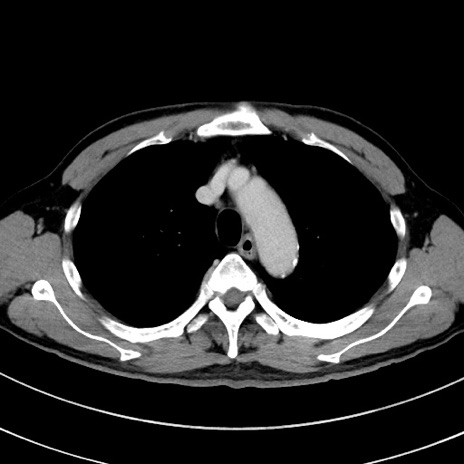

症例8(横断像)

【症例】 60歳代男性

【主訴】 黒色吐物

【現病歴】 4日前から嘔気自覚、2日前の朝食後にも嘔気あり、自分で手で嘔吐反射起こし嘔吐したところ血が混ざっていたため受診。

【既往歴】 5年前汎発性腹膜炎を伴う急性虫垂炎で手術、高血圧、前立腺肥大症、高脂血症

【身体所見】 腹部正中に手術癩痕あり 腹部平坦・軟圧痛なし膨満感あり

【データ】WBC 8400、CRP 4.54